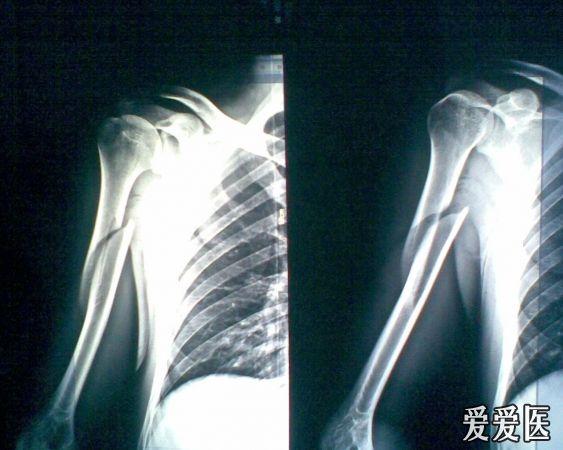

螺旋形骨折的图片,骨折分类

我是六月十八号摔着的,胫骨远端螺旋形骨折,下图是九月三号拍的片子

90岁股骨远端长螺旋形骨折

肱骨骨折术后六周求助(附片)

右胫骨螺旋形骨折,2.右腓骨下段